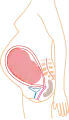

De acuerdo a su desarrollo, el embarazo se suele dividir en tres etapas de tres meses cada una, con el objetivo de simplificar la referencia a los diferentes estados de desarrollo del feto.

El tercer trimestre marca el principio de la viabilidad —aproximadamente después de la semana 25— que quiere decir que el feto podría llegar a sobrevivir de ocurrir un parto prematuro, parto normal o cesárea. Ya que a partir de este momento los pulmones fetales se encuentran formados casi totalmente, solo les falta madurar.

Mes 7: Mide 30 cm y pesa 1500 g. Comienzan a moverse los pulmones. Aumenta la grasa subcutánea y ya no cabe bien en el útero. Mes 8: Mide 35 cm y pesa 2500 g. Generalmente se pone boca abajo (posición cefálica) Se engrosa la piel, adquiriendo el tono rosáceo que tendrá definitivamente.

Mes 8: Mide 35 cm y pesa 2500 g. Generalmente se pone boca abajo (posición cefálica) Se engrosa la piel, adquiriendo el tono rosáceo que tendrá definitivamente. Mes 9: Mide 50 cm y pesa aproximadamente 3000 g. Los pulmones ya están completamente formados para la vida exterior. Se cae el lanugo y la piel se estira.

Mes 9: Mide 50 cm y pesa aproximadamente 3000 g. Los pulmones ya están completamente formados para la vida exterior. Se cae el lanugo y la piel se estira.